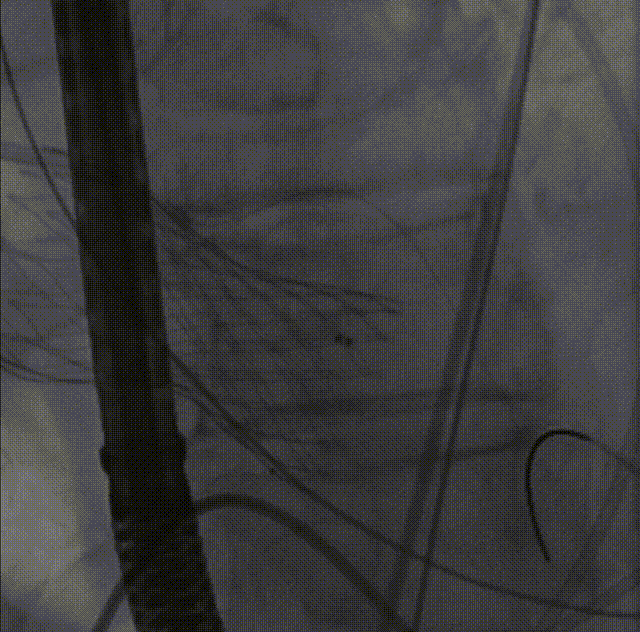

26VenusAplus+snare

瓣膜内22mm球囊后扩张,左冠无显影

LM烟囱支架植入4.0*30mm